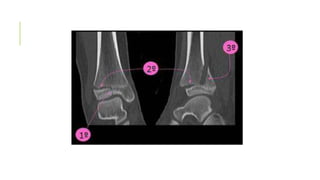

Radiografía 2

proyecciones

Rx

comparativa

DIAGNÓSTICO SALTER RB. TRASTORNOSY LESIONES DEL SISTEMA MUSCULOESQUELÉTICO. 3ª ED. MÉXICO: ELSEVIER-MASSON. Tumefacción Dolor local Radiografía 2 proyecciones Rx comparativa Cerca del extremo de un hueso largo

Extraarticulares Intraarticulares No visible enRX. DAVID J MATHISON. GENERAL PRINCIPLES OF FRACTURE MANAGEMENT: FRACTURE PATTERNS AND DESCRIPTION IN CHILDREN. IN: UPTODATE, WALTHAM, MA (JUNE 18, 2015).